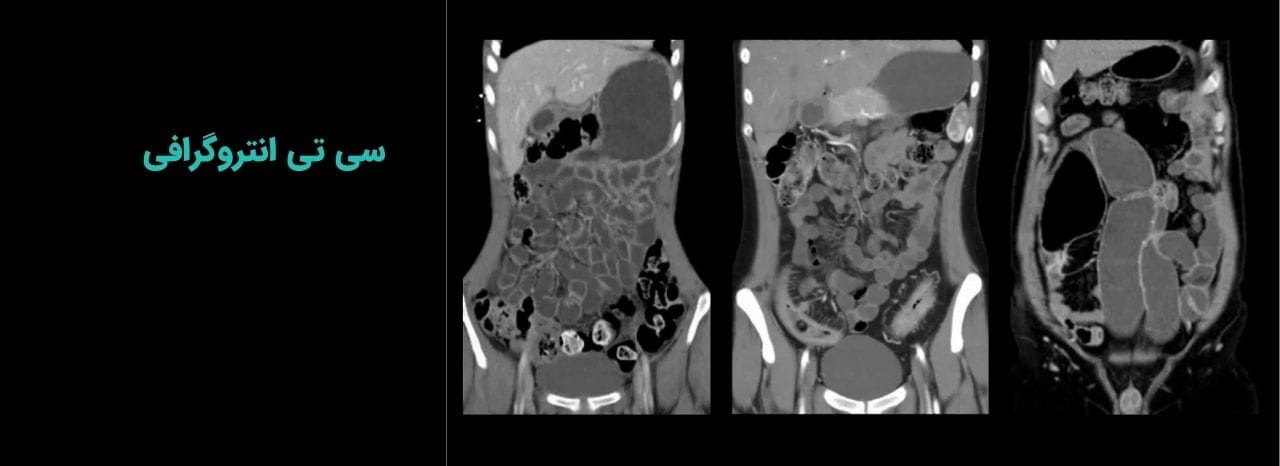

سی تی انتروگرافی (CT Enterography) با بهرهگیری از تکنولوژی پیشرفته اسکن مولتی دتکتور و با تزریق ماده حاجب، روش تشخیصی پیشرفته برای بررسی مشکلات و پیچیدگیهای روده باریک است. این روش تصویربرداری دقیق، با غلبه بر محدودیتهای روشهای سنتی، امکان ارزیابی جامع ضایعات و بافتهای اطراف را بدون نیاز به روشهای تهاجمی فراهم میکند.

سی تی انتروگرافی یکی از پیشرفتهترین و دقیقترین روشهای سی تی اسکن روده باریک است که تصاویری با وضوح بسیار بالا و به صورت سه بعدی از این عضو حیاتی فراهم میکند.